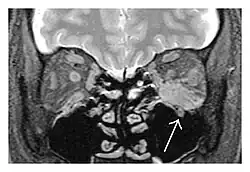

The extent of inflammation that can occur in IgG4-ROD is well demonstrated on magnetic resonance imaging (MRI).

Infraorbital nerve enlargement (IONE) is considered to be a particularly suspicious sign of IgG4-ROD, but seems to occur only when inflammation is in direct contact with the infraorbital canal.[10] IONE is defined as the infraorbital nerve diameter being greater than the optic nerve diameter in the coronal plane.